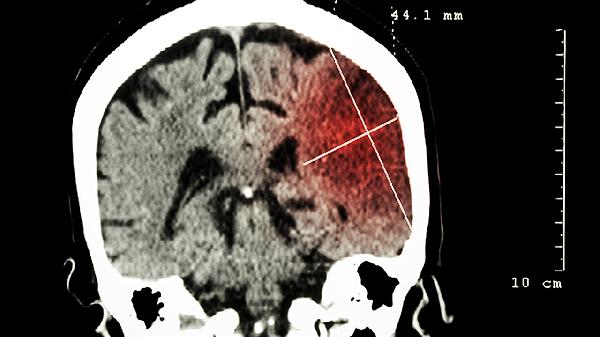

CT通过X线断层扫描显示脑部结构异常,对直径超过5毫米的肿瘤通常可识别。高密度病灶如脑膜瘤、胶质母细胞瘤因与正常脑组织对比明显,检出率较高。伴有出血或钙化的肿瘤在CT图像上呈特征性高信号,诊断准确性提升。对于疑似病例,CT增强扫描可进一步观察血供情况,辅助判断肿瘤性质。

部分低密度肿瘤如星形细胞瘤早期可能仅表现为轻微脑水肿,CT平扫易漏诊。位于颅底或脑干的小型肿瘤因骨骼伪影干扰,检出率降低。对于这类情况,MRI因其多参数成像优势成为更精准的检查手段。CT对软组织结构分辨率有限,难以区分肿瘤与周围水肿带,可能影响大小测量的精确性。